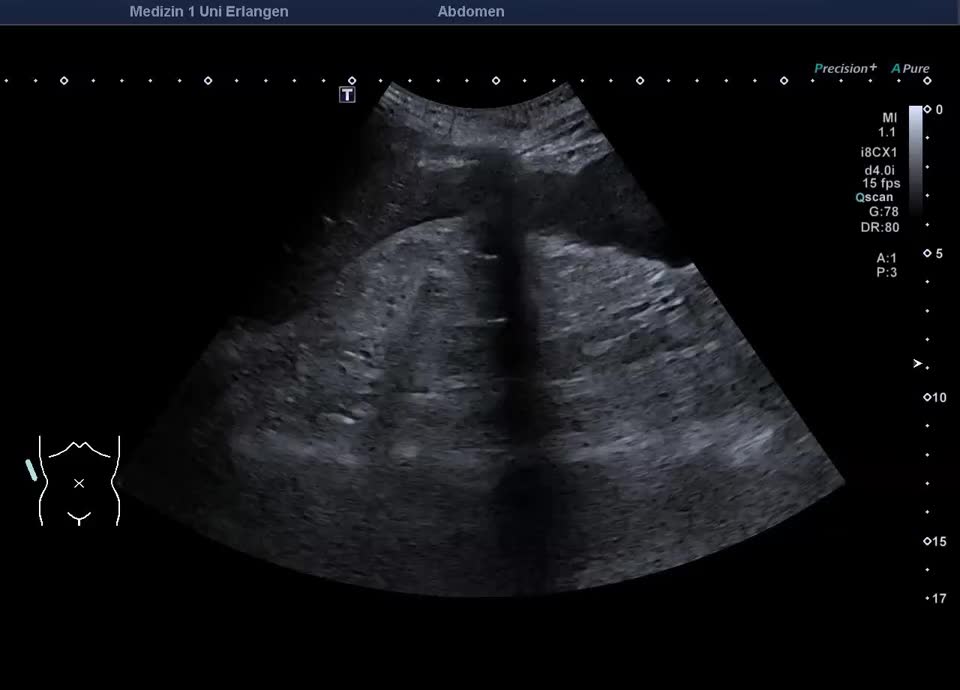

Chronische Nierenerkrankung

• Chronische Nierenerkrankung